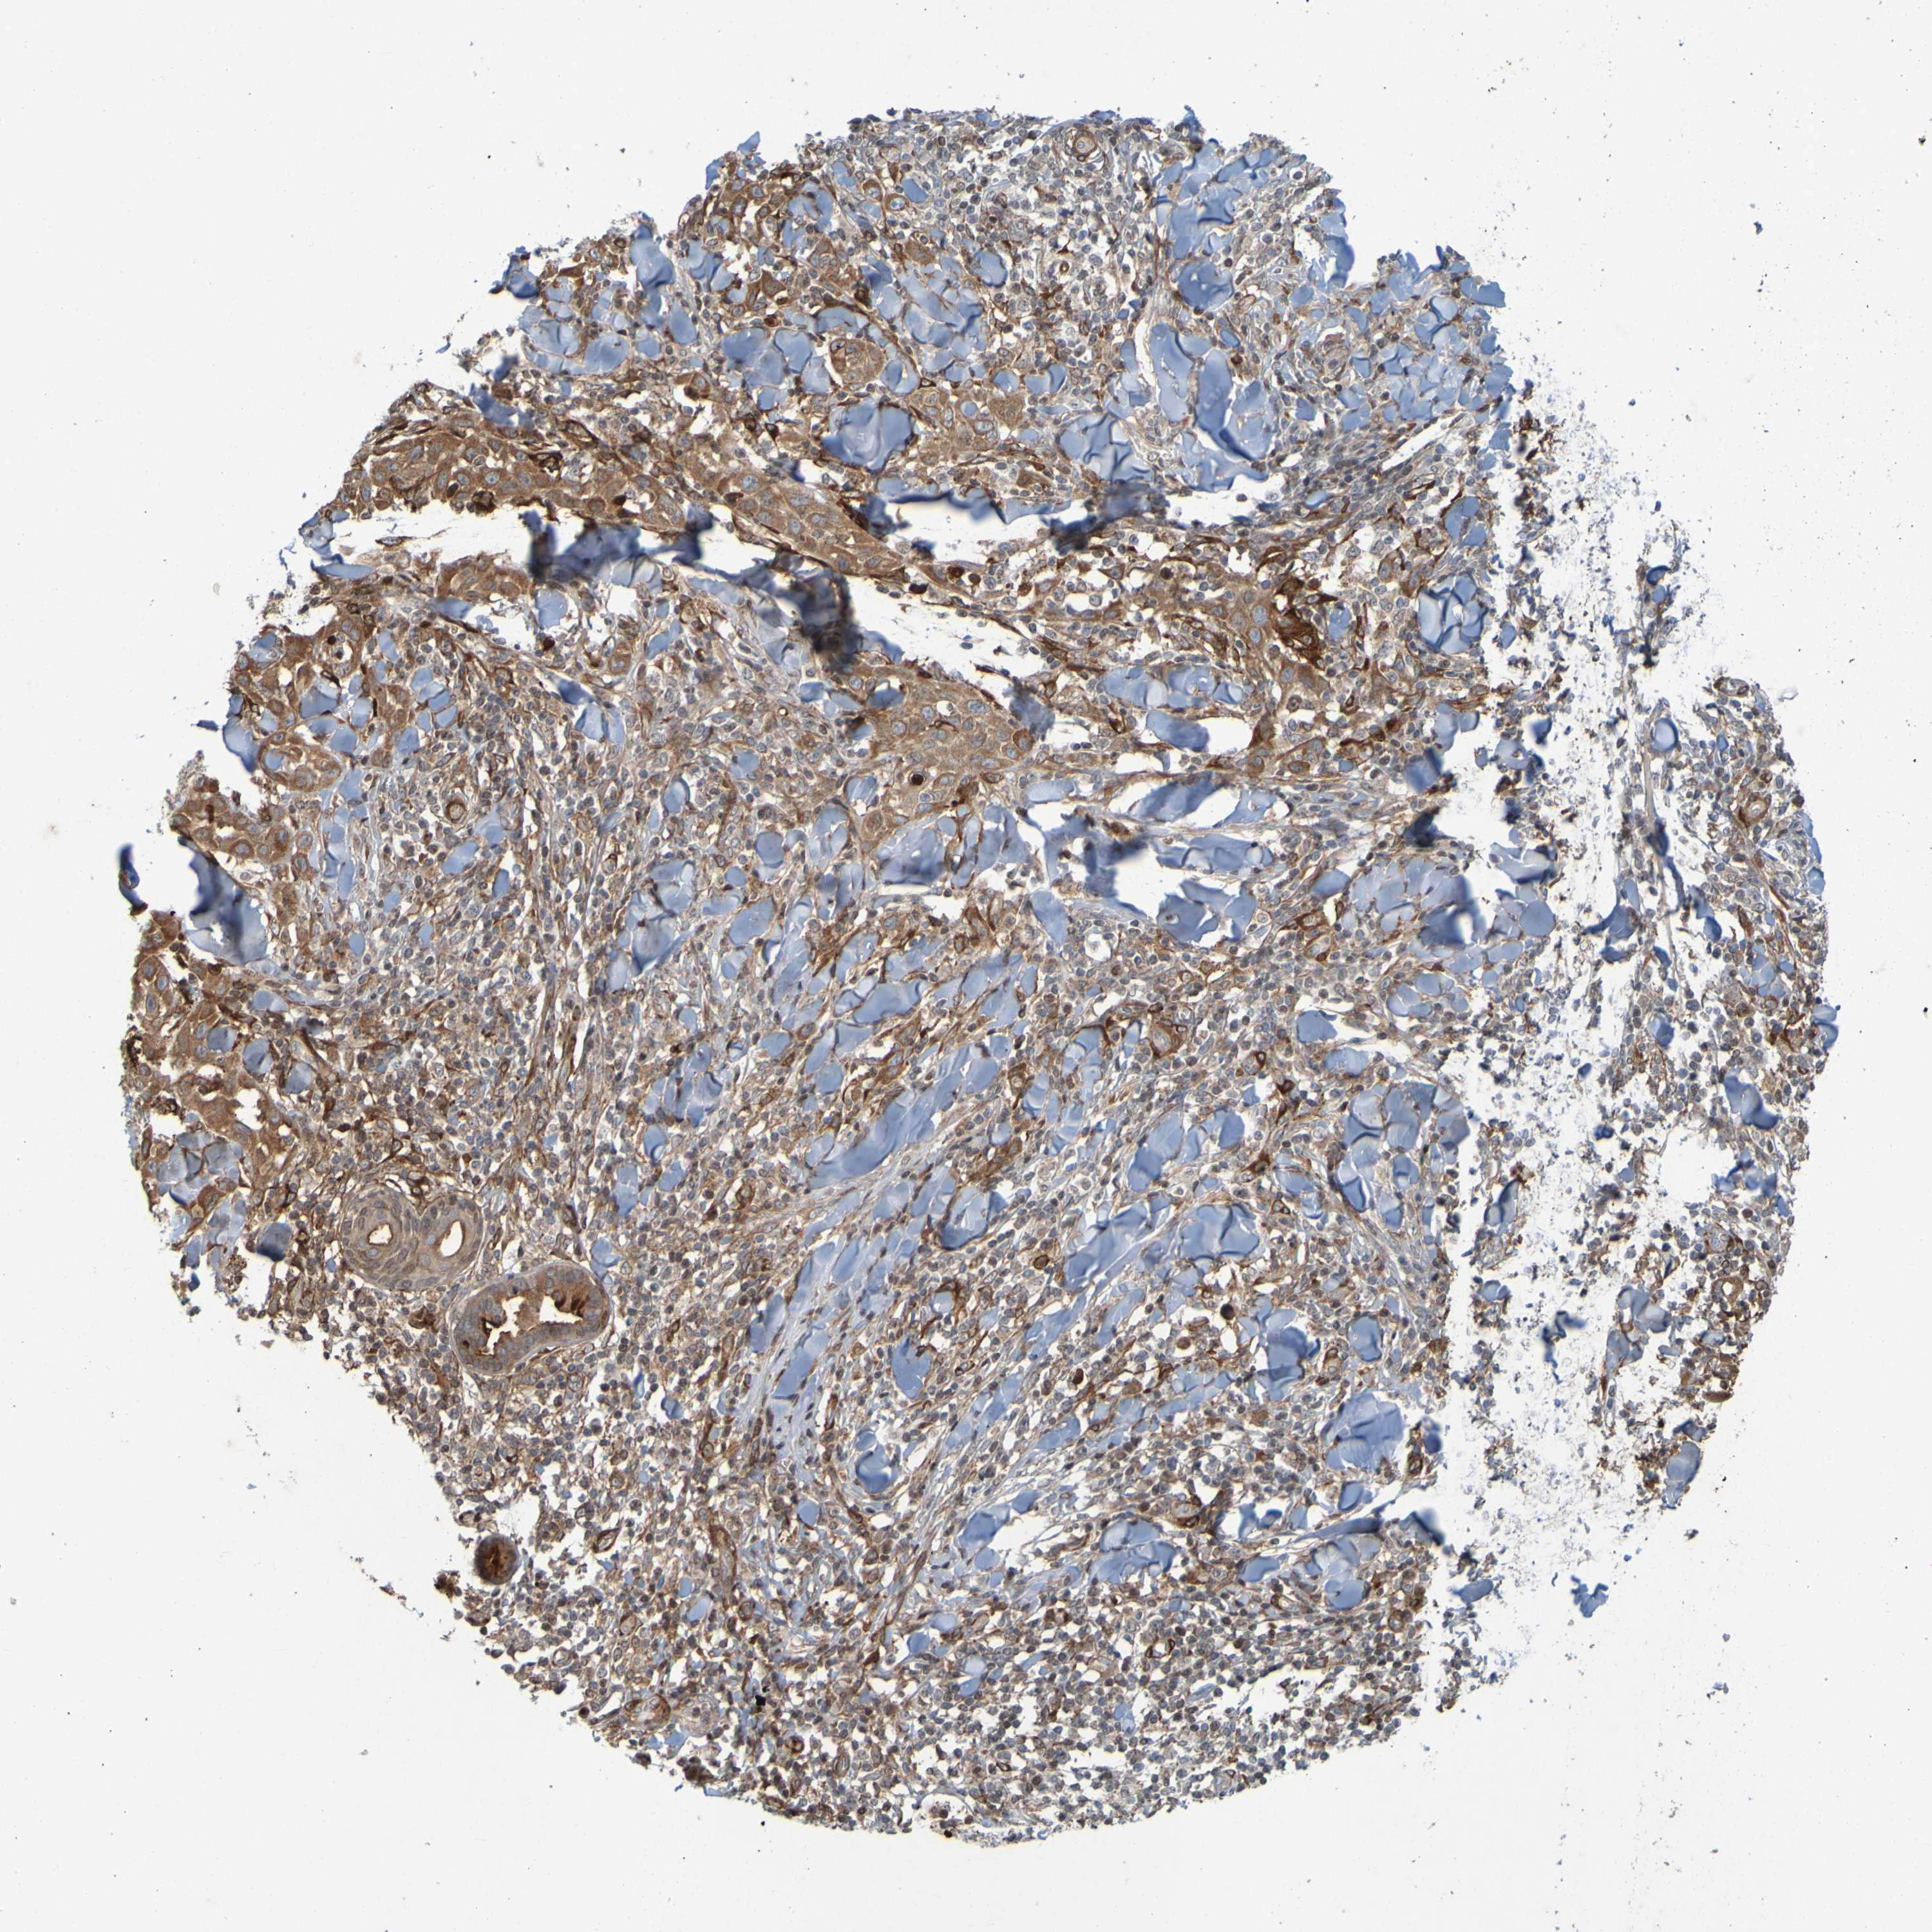

CANCER SKIN CANCER Show tissue menu

Basal cell and squamous cell cancer

SKIN CANCER - Protein expressioni

A mouse-over function shows sample information and annotation data. Click on an image to view it in a full screen mode. Samples can be filtered based on level of antibody staining by selecting one or several of the following categories: high, medium, low and not detected. The assay and annotation is described here.

Antibody stainingi

Antibody staining in the annotated cell types in the current human tissue is reported as not detected, low, medium, or high, based on conventional immunohistochemistry profiling in selected tissues. This score is based on the combination of the staining intensity and fraction of stained cells.

Each image is clickable and will lead to virtual microscopy that enables deeper exploration of all samples and also displays staining intensity scores, fraction scores and subcellular localization as well as patient and tissue information for each sample.

Antibody HPA056004

Antibody CAB010887

Staining

High

Medium

Low

Not detected

Intensity

Strong

Moderate

Weak

Negative

Quantity

>75%

75%-25%

<25%

None

Location

Nuclear

Cytoplasmic/membranous

Cytoplasmic/membranous,nuclear

Basal cell carcinoma

Squamous cell carcinoma, NOS

Adnexal tumor, benign